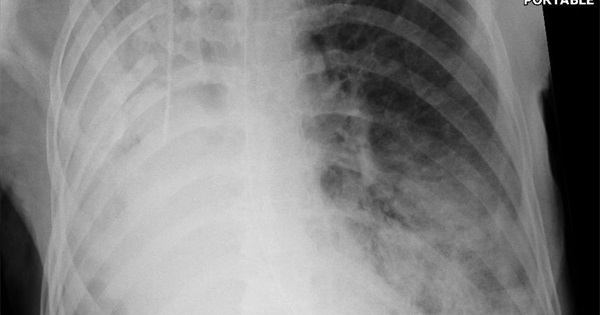

Фотографии и инфографика о пневмонии: симптомы, лечение и статистика